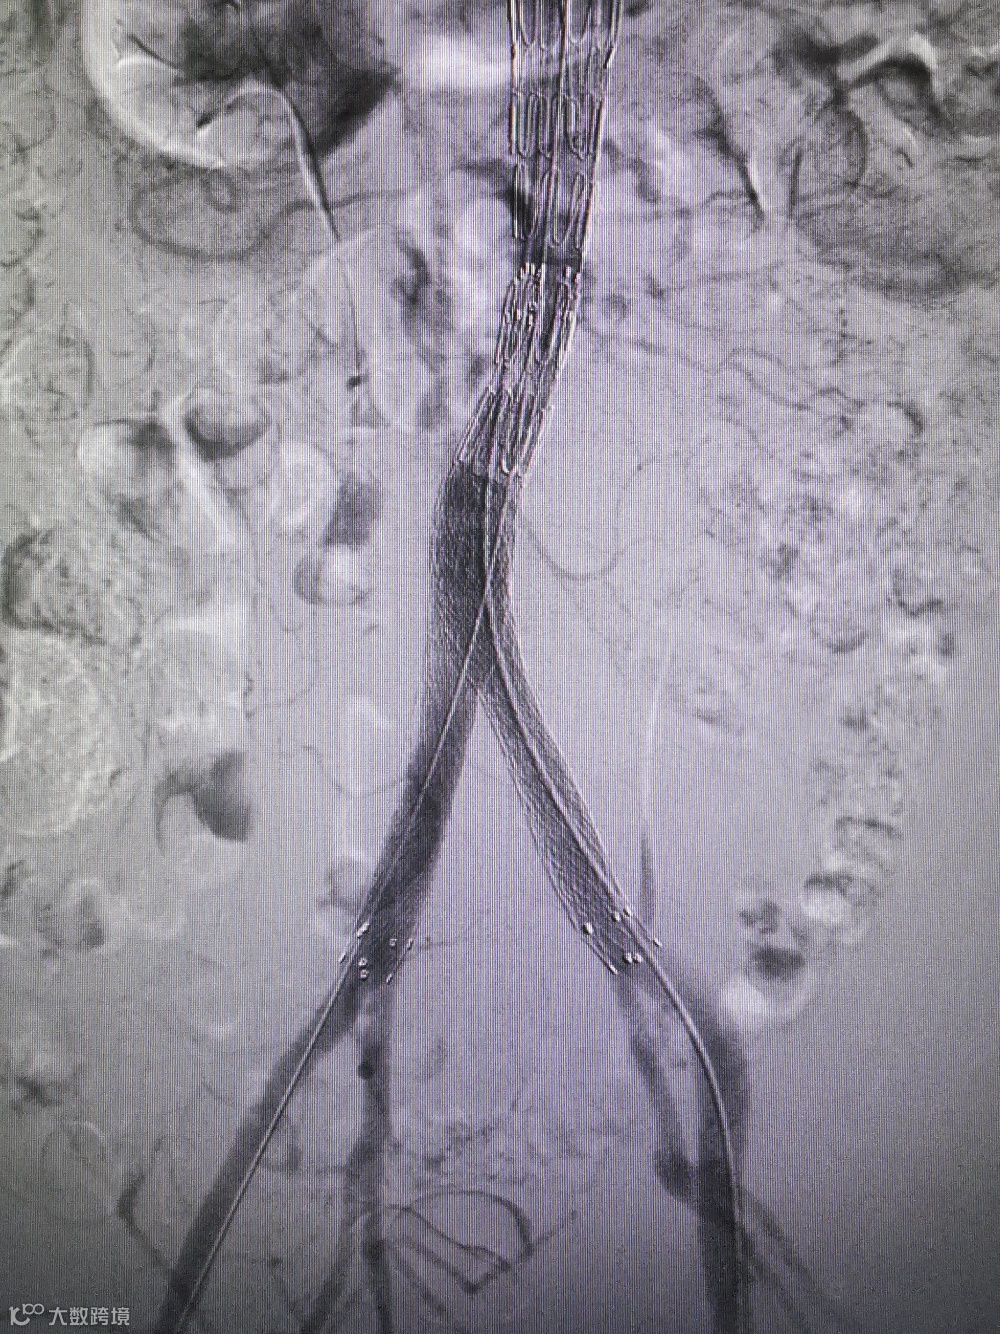

Separator With Aspiration catheter for Mechanical Thrombectomy(MT)【分离器辅助导管抽吸技术】:旨在提高整体系统的抽吸效率和治疗安全性,快速帮助血栓清除。

1)抽吸导管头端堵管,分离器可以快速疏通导管,降低撤管冲洗的频率。

2)针对大负荷血栓或亚急性血栓,分离器辅助下抽吸能提升整体系统抽吸效率,缩短手术时间。

手术过程